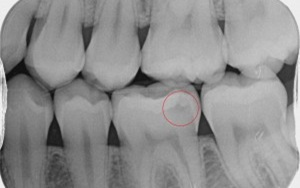

These pictures are a case example of a cosmetic tooth-coloured filling done here at Cornerstone Dental.

Step 1